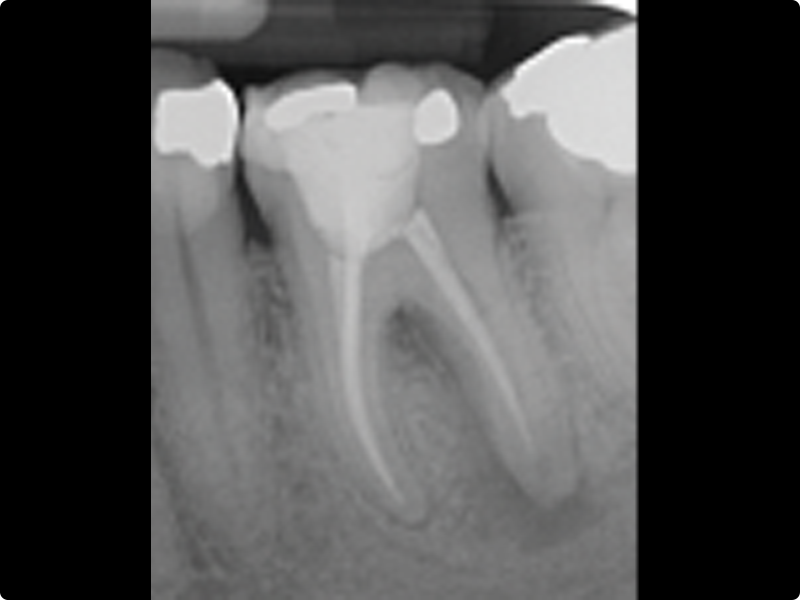

• Root canal filling: general principles

• Endodontic seal: warm vertical condensation, carrier-based systems, bioceramic sealers

• Root canal filling

• Backfilling with thermoplasticized gutta-percha